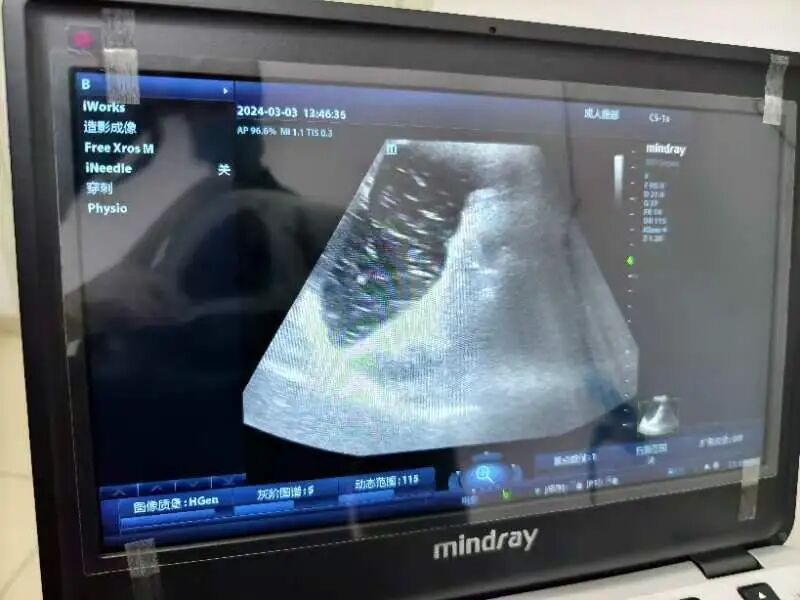

目前,传统洗胃机给患者洗胃时的压力设定、送液与出液转换都是自身控制,它会在短时间、高速度、大流量地给病人送液,高压的水流长时间反复地冲洗可以导致胃粘膜充血、溃疡,甚至出血,进而导致胃穿孔、胃破裂,洗胃液进出胃的液量以及是否达到溶解药物、毒物或食物的作用、是否将存留于胃中的药物、毒物或食物清洗干净、是否导致存留于胃中的药物、毒物或食物进入肠道等关键环节都是凭借临床经验。然而,超声引导下洗胃能观测到洗胃管是否在胃内、胃内情况,从而对胃肠减压监护。

超声引导下洗胃是指在超声设备的辅助下,通过插入胃管进行洗胃操作。超声技术能够实时观察胃内情况,确保洗胃操作的安全性和有效性。